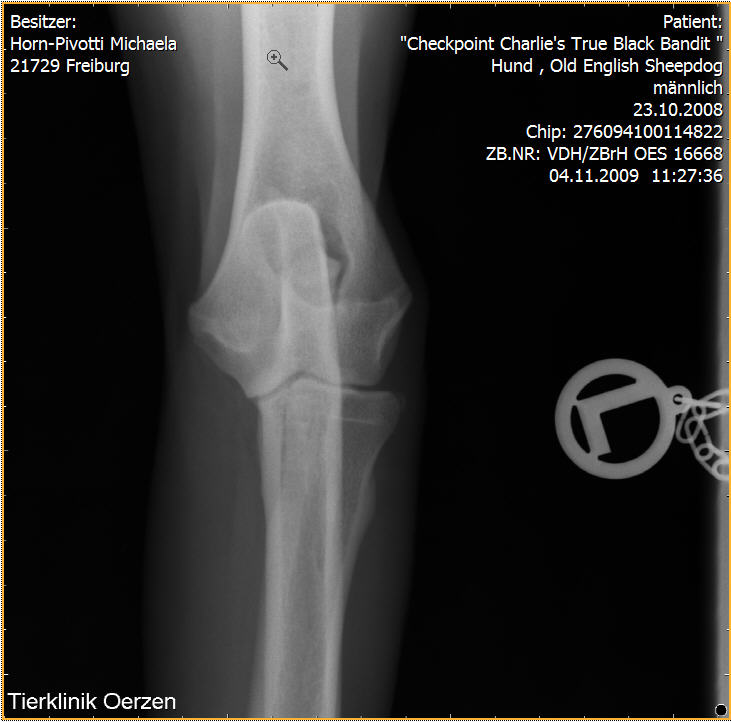

Röntgenaufnahmen HD/ED “Checkpoint Charlie’s True Black Bandit”